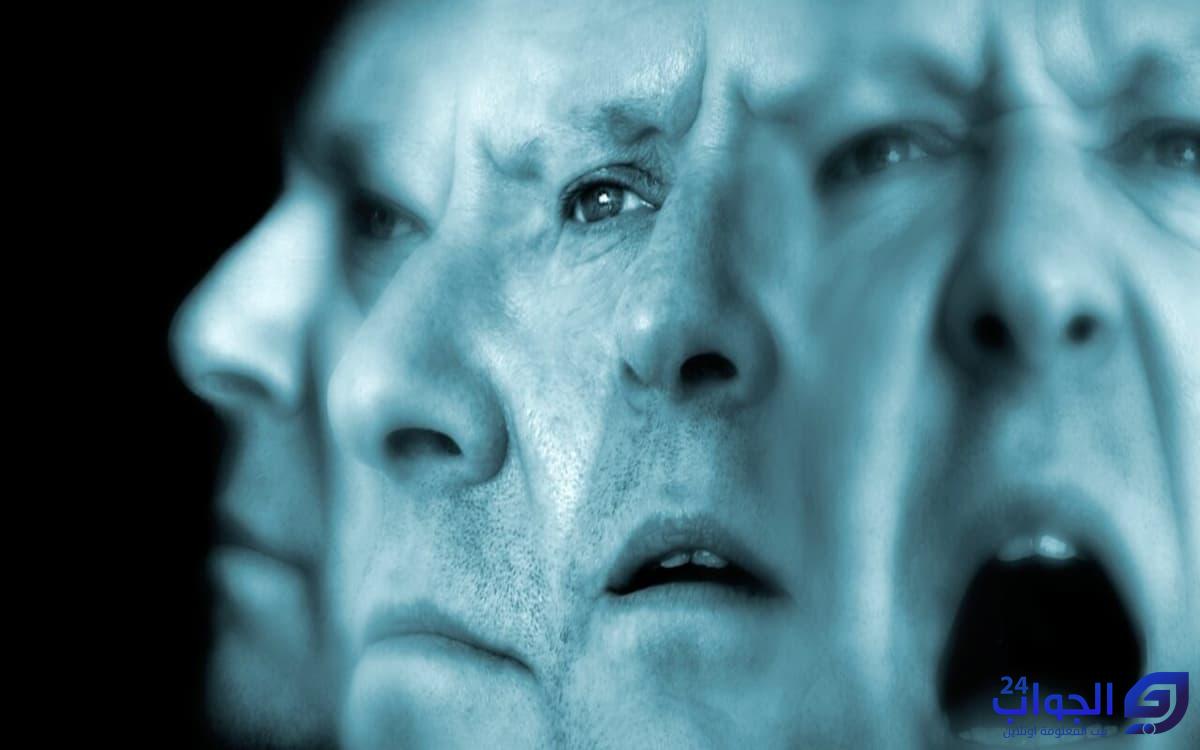

- تشتت الذهن وصعوبة في التفكير